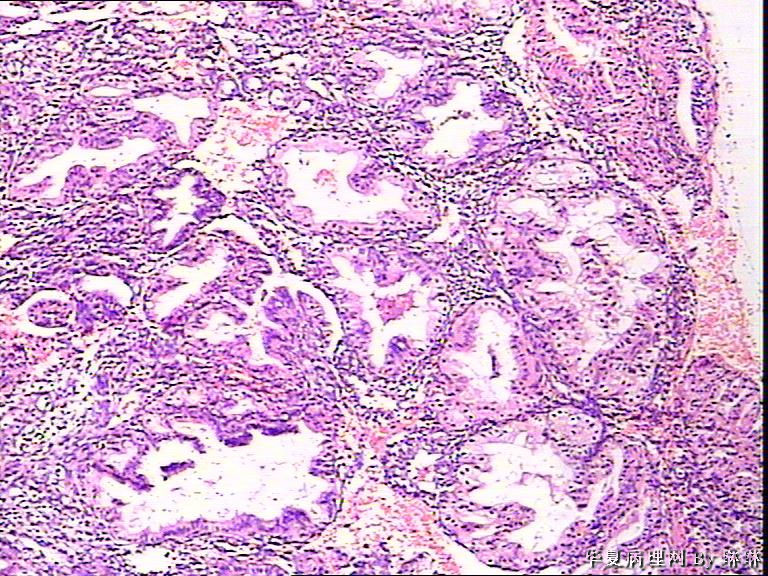

患者女性,38岁,月经量多4个月,曾服用止血药物,无其他病史。

• 子宫内膜,请教图1

图1

腺体呈高度分泌反应,我们必须结合病史,考虑是否药源性反应,或持续黄体期子宫内膜.

晚泌期宫内膜,并见A-S现象

开始临床没有提供怀孕的病史,后来我们有咨询临床科室,大夫还是说没有用药、月经正常,刚过了经期,月经量多,这次月经持续时间长入院。所以我们开始排除了高度分泌的A-S反应,看到腺体增生呈乳头状,还有异型性,而且镜下部分子宫内膜还有增生期改变的,不完全是高度分泌的。再三考虑后还是要求临床查了血HCG,结果显示HCG370多。最后我们发了单纯性增生伴高度分泌。

A-S反应?

复杂性增生伴分泌反应

我是新手,仅仅做为参考:   分泌反应子宫内膜

A-S反应